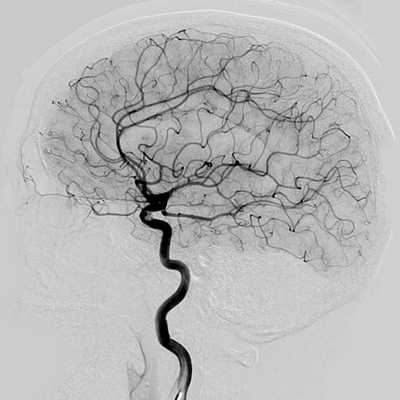

Отличия МРТ и КТ ангиографии от классической ангиографии

МРТ и КТ ангиографию не следует путать с прямой ангиографией. Классическая ангиография - это технологически простой метод исследования. Он появился в 1927 году, когда португальский невролог доктор Мониц провел первое ангиографическое исследование с введением контрастного вещества. Долгое время этот метод оставался золотым стандартом обследования сосудов головы, сердца, позвоночника, шеи, нижних конечностей и брюшной аорты. Основным недостатком данного вида ангиографии является необходимость сделать механический прокол сосудов (сонной или бедренной артерии), чтобы ввести контрастное вещество и обследующее устройство. Прямая АГ- это, в конечном счете, инвазивная манипуляция, требующая госпитализации и имеющая определенный риск осложнений. Кроме того, классическая ангиография дает возможность делать ангиограммы только в прямой или боковой проекции.

У прямой агиографии есть и диагностические ограничения. С ее помощью врач может достаточно подробно рассмотреть сами сосудистые аномалии (стеноз, окклюзии), но по ней нельзя получить информацию о мальформациях артерий, тромбозах вен, характере кровоизлияния при инсульте, состоянии вещества головного мозга. Для этого потребуется КТ или МРТ сосудов головного мозга.